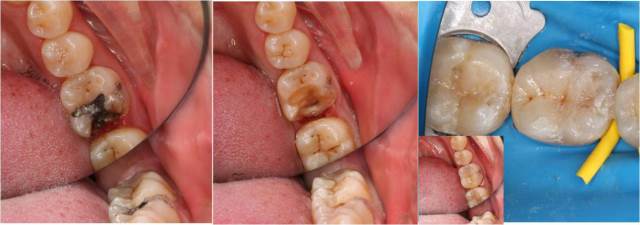

图:龋坏、继发龋坏、牙体缺损的直接美学修复

图:牙体牙髓冠根一体化治疗方案,一站式解决患者牙体及牙髓病的治疗需求

科室全面开展显微牙体牙髓一体化治疗,由根到冠一站式解决整颗患牙的治疗需求。以患牙的功能为目的设计治疗方案,在完善根管治疗后即时进行牙冠缺损的修复,包括直接充填、嵌体/全冠修复等,保证根管治疗的疗效。最大限度地节省患者的治疗时间,减少复诊次数,并提高治疗的成功率。